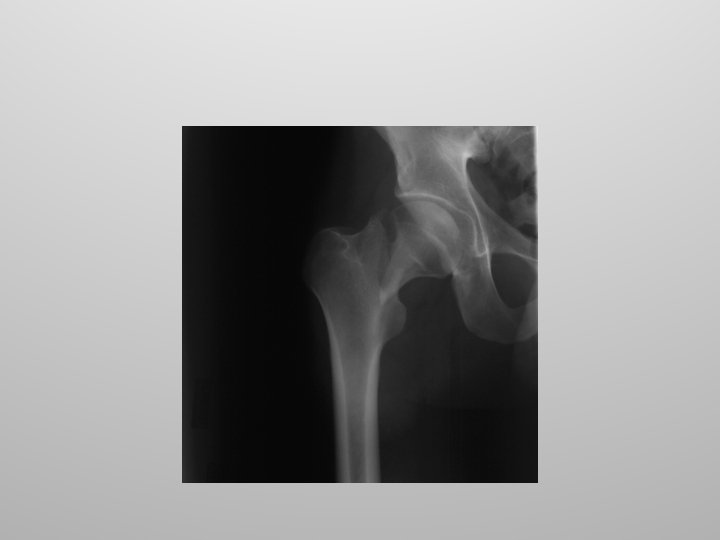

Hip Injuries Common injuries to the hip joint include fractures and dislocations. Hip fractures typically involve the neck of the femur and are the result of underlying disease such as osteoporosis.

Hip Replacement Hip replacement surgery, also called total hip arthroplasty, involves removing a diseased hip joint and replacing it with an artificial joint, called a prosthesis.

Hip Replacement Hip replacement is typically used for people with hip joint damage from arthritis or an injury. Followed by rehabilitation, hip replacement can relieve pain and restore range of motion and function of your hip joint Lets do a hip replacement!